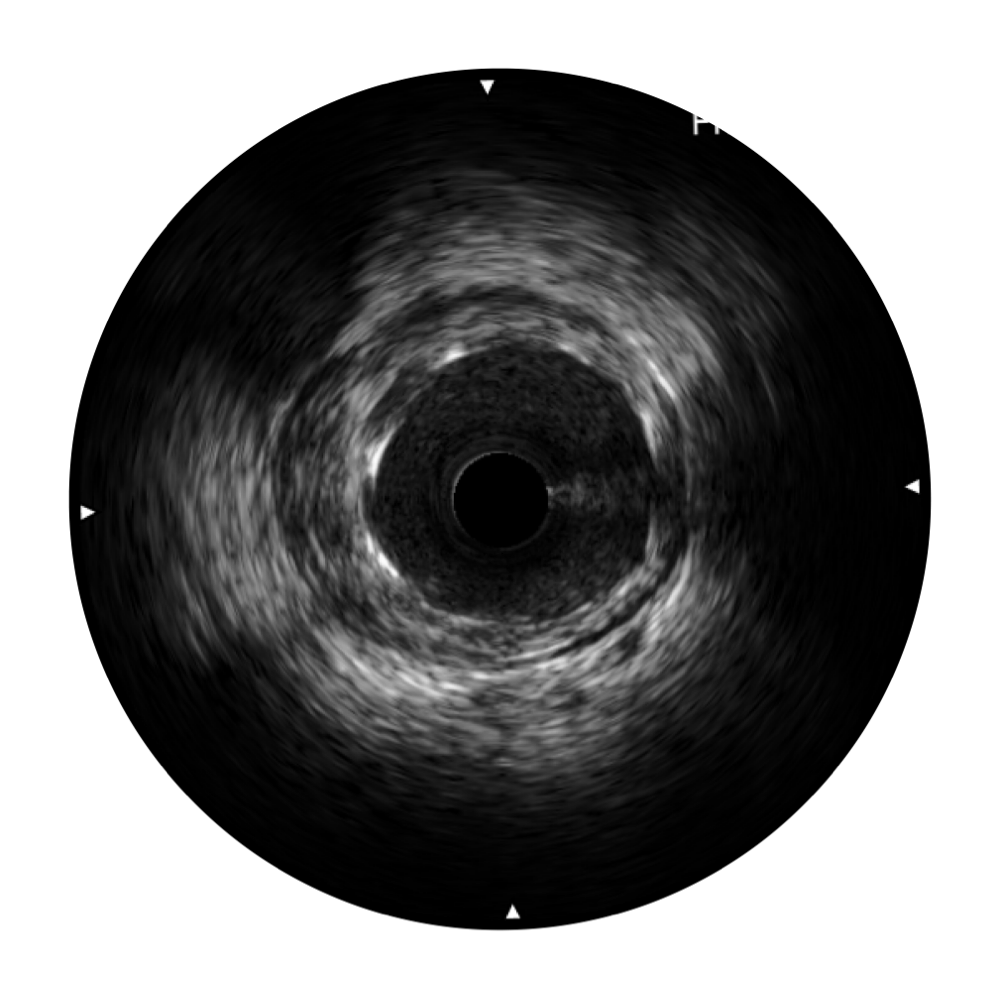

• 乐玩lewin国际宽频IVUS图像

对比传统IVUS导管成像,乐玩lewin国际宽频IVUS图像的近场支架梁显影更细腻,远场中膜外血管仍清晰可辨,兼顾远中近,兼顾分辨力与穿透深度